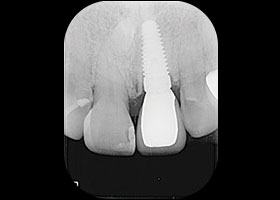

假牙拆除前的X光片,可看出假牙已不密合。

植牙後,裝上臨時性假牙X光片。

假牙完成X光片。